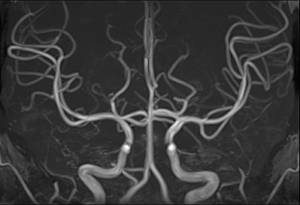

MRA(MRアンギオ)では、造影剤を注射しなくても血管を画像化することができます。脳血管などに動脈瘤(血管のこぶ)や狭窄(細くなっている部分)がないか精密検査をすることができます。